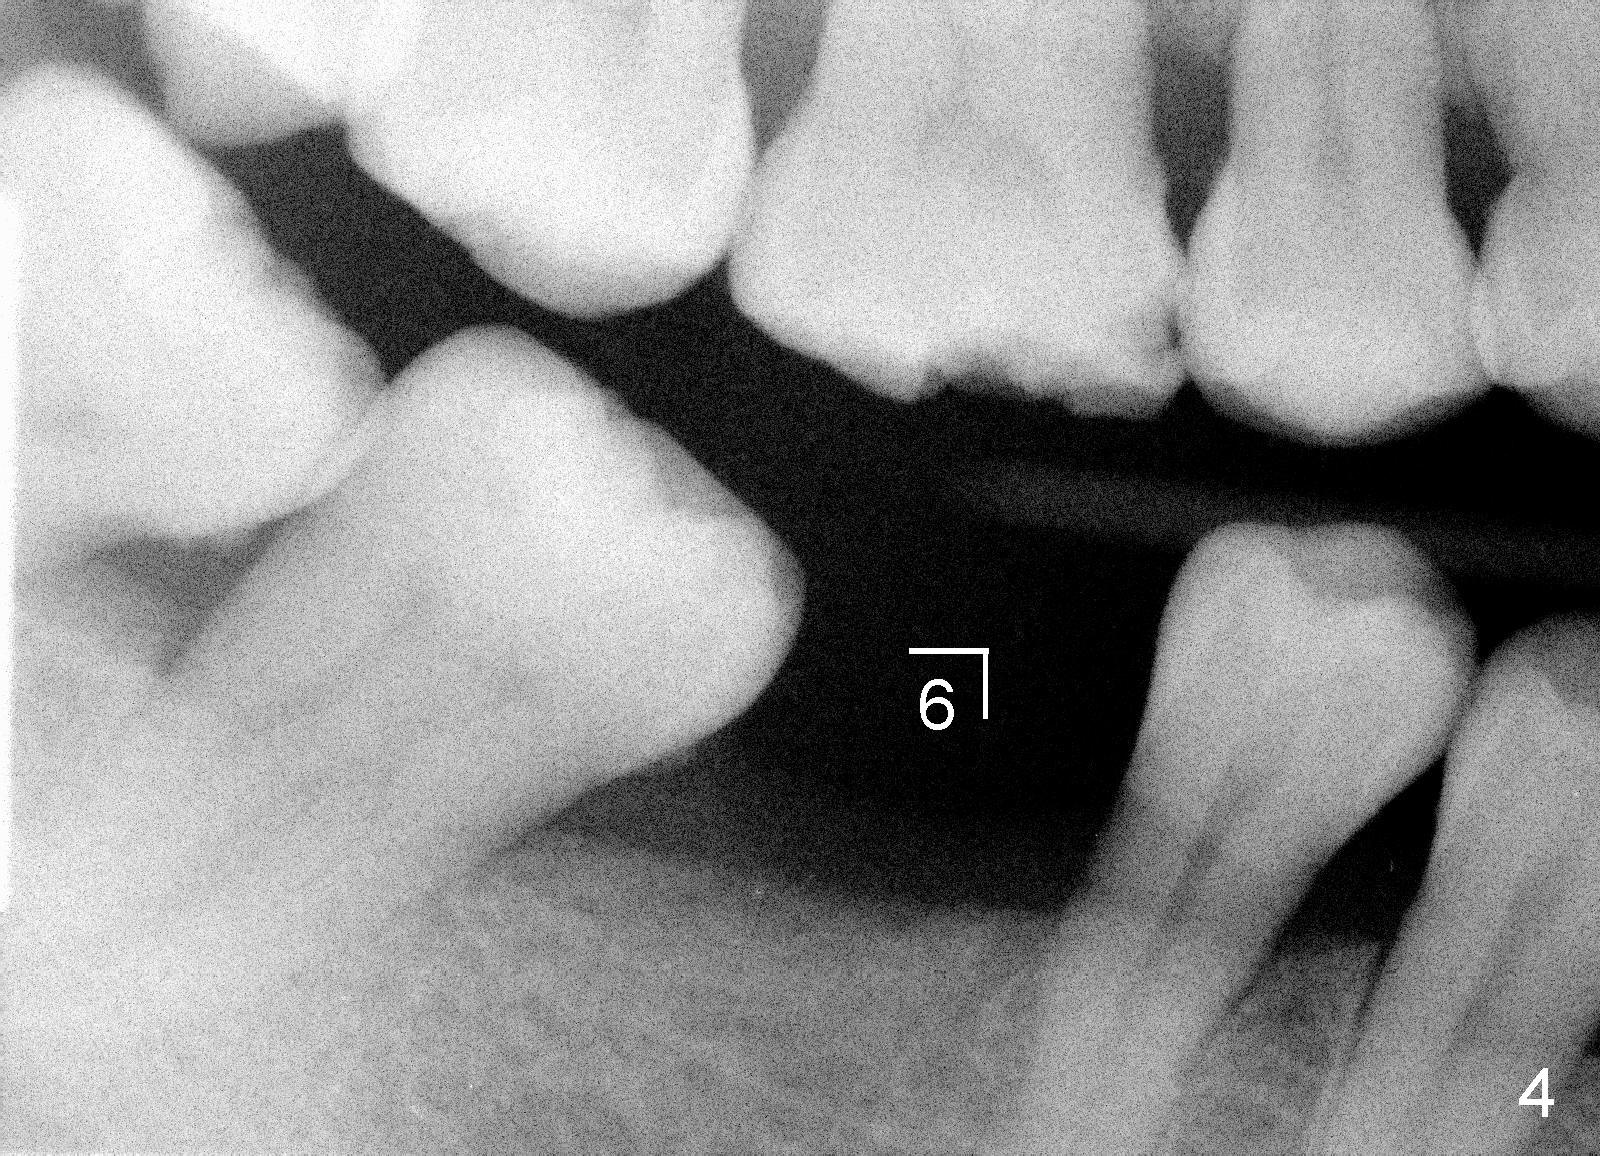

A 44-year-old lady has lost two of the 1st molars (upper left (Fig.1-3) and lower right (Fig.4-6)) for several years. Fig.1,4 are preop PAs, Fig.2,5 CT sagittal sections, and Fig.3,6 CT coronal sections. The adjacent teeth shift and tilt into the edentulous space.